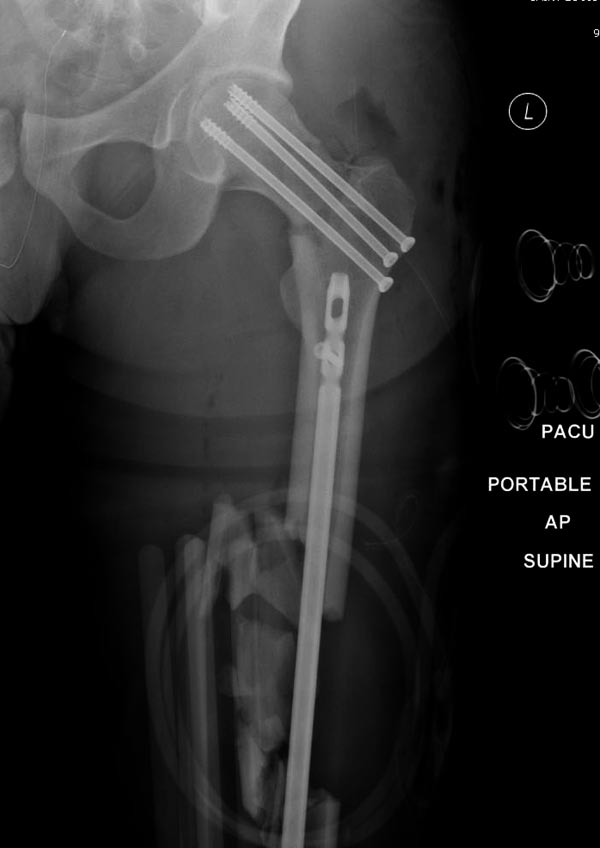

Здесь выставлен ренгенограммы больного, ему 21, травму получил в

результате высокоскоростной погони на украденной машине, которая

закончилась смертью трех остальных“боевых комрадов”. Начатую коллегой

открытую операцию на шейке пришлось закончить мне, установкой винтов и

ретроградной фиксацией бедра. Выписка в обычное сроки и наблюдался

амбулаторно. Каждый раз напоминали о возможности осложнений ввиде

несращения! По истечению 4 месяцев появились признаки варусной

деформации. На СТ срезах несращение шейки и бедра. Риминг, замена на

более толстый гвоздь и вальгусная остеотомия.